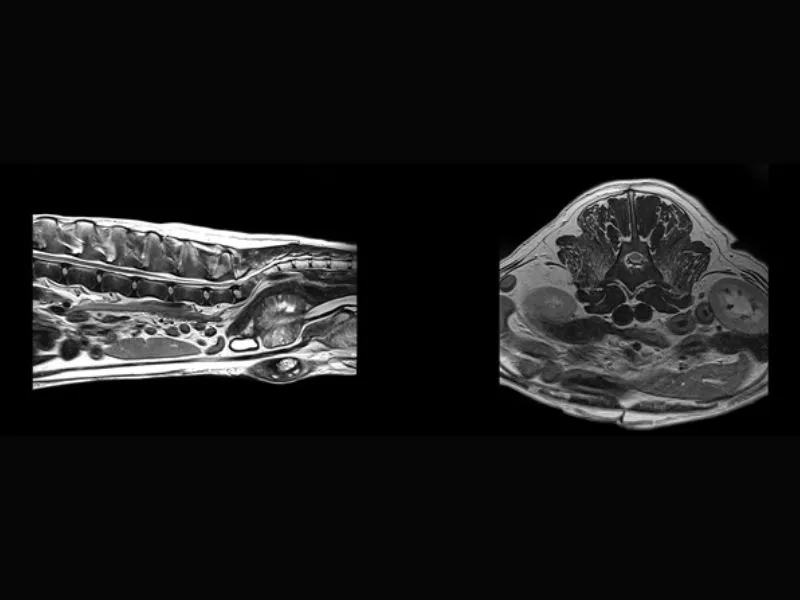

Clinical images

Small animals